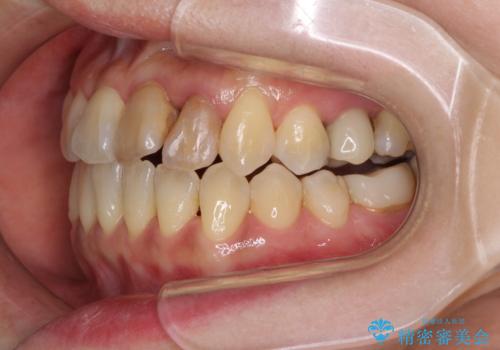

反対咬合で痛む前歯を改善 インビザラインによる矯正治療

- 前歯の反対咬合により、日々強い痛みを感じているとのことで来院された患者様です。

骨格的に下顎が前方位にありますが、歯列矯正で前歯の被蓋関係を改善することができると判断されたため、インビザラインにより矯正治療を行うこととしました。

また、上顎前歯と下顎大臼歯に神経を取り除いた歯があったため、矯正治療後に、セラミッククラウンにて補綴することとしました。

前歯が内側に倒れ込む力がかかり、正常な歯ぎしりもできないため、非常に負担のかかりやすい咬み合わせでした。

矯正治療中に上顎前歯が下顎前歯を乗り越える際は、前歯でしか咬めない状況が続くため、食事など不便を感じましたが、治療後には前歯の痛みもなくなり、安定した咬み合わせとなりました。